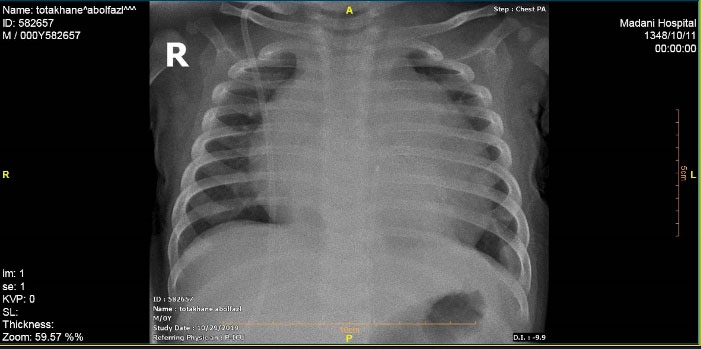

A male infant who underwent VP implantation due to congenital hydrocephalus at the age of 2-month-old presented with fever and lethargy at the age of 8-month-old. Pericardial effusion was detected in transthoracic echocardiography and plain chest radiography (), and he underwent pericardial window under general anesthesia and a mediastinal chest drain was implanted in the pericardial space. After draining the excessive pericardial fluid, the mediastinal chest drain was removed and the patient was discharged under appropriate conditions. The patient presented again at 11 months of age due to fever, lethargy, recurrent vomiting, and respiratory distress. In chest radiography migration of the distal end of VP catheter into mediastinum was suspected. More evaluation by transthoracic echocardiography (TTE) showed the entrance of catheter into right ventricle after perforating the diaphragm and pericardium. Meanwhile a mass lesion at tip of catheter was detected in favor of vegetation and endocarditis ().

Figure 1. Plain chest radiography depicting pericardial effusion (at the age of 8 month old).